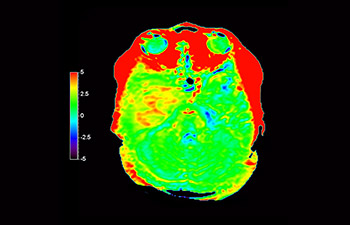

3D APT (Amide Proton Transfer) ist eine einzigartige, kontrastmittelfreie Methode zur MR-Tomographie des Gehirns, die den Bedarf nach einer sichereren Diagnose in der Neuroonkologie erfüllt. 3D APT nutzt das Vorhandensein von endogenen zellulären Proteinen zur Erzeugung eines MR-Signals, das direkt mit der Zellproliferation, einem Marker für Tumoraktivität, korreliert. 3D APT kann geschulte medizinische Fachkräfte dabei unterstützen, gering differenzierte von hochdifferenzierten Gliomen und Tumorverhalten von Behandlungseffekt zu unterscheiden1.

Rezidivierendes Glioblastom

Aufnahme des Gehirns zur Untersuchung auf ein rezidivierendes Glioblastom

mit 3D APT